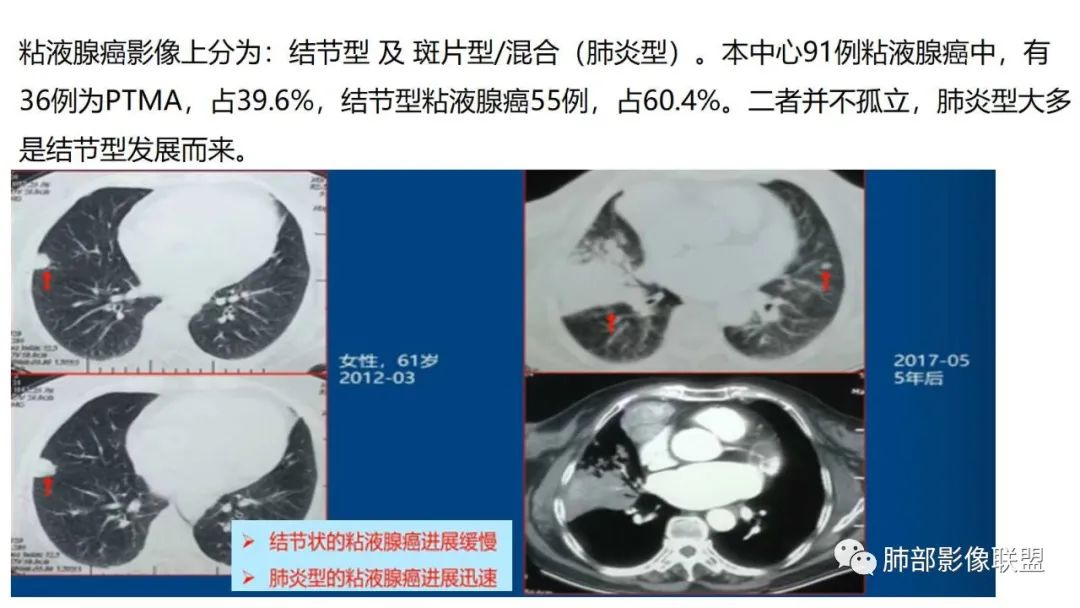

粘液腺癌影像上分为:结节型及斑片型/混合(肺炎型)。

一、结节型粘液腺癌和普通腺癌类似,重视体检及复查不易遗漏

3.结节型发展缓慢,淋巴结转移少见。

二、肺炎型

2、病灶常有一个主病灶,常位于下肺。后沿气道播散为多发病灶。

9.粘液腺癌的变化规律:结节缓慢发展而来,向周围播散形成斑片后可快速进展,有时支气管镜后或粘液排出后局部可形成好转的假象。病灶可沿肺泡和支气管播散。